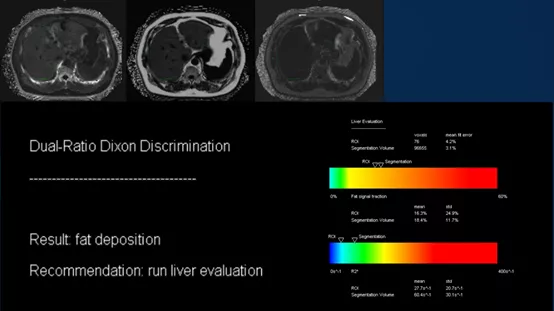

多回波DIXON技术:分割全肝扫描定量分析,肝脏存在脂肪浸润,全肝肝脏脂肪含量平均为18.4%,ROI区域内肝脏脂肪含量平均为16.3%;HISTO序列波普分析:感兴趣区内测定肝脏脂肪含量为21.4%。

结论:全肝脂肪定量分析提示肝脏脂肪浸润,结合波普感兴趣区测定肝脏脂肪含量,综合考虑为中度脂肪肝(≥10%且<25%)。

用药3个疗程后,再次复查,肝脏平均脂肪含量减少,感兴趣区肝脏脂肪含量减少,数据表明用药具有效果。